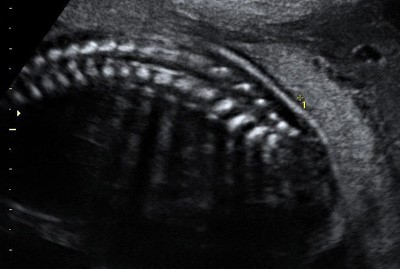

Позвоночник плода на 21-й неделе беременности в режиме 2D